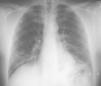

La neumonía eosinófila crónica (NEC) es una entidad poco frecuente. Evoluciona de forma subaguda o crónica. Los síntomas incluyen disnea, tos, pérdida de peso y fiebre. La eosinofilia es característica. Radiológicamente cursa con infiltrados alveolares periféricos de predominio en lóbulos superiores. El tratamiento se basa en corticoids durante 6-8 meses.

ConclusionesLa NEC es una enfermedad infrecuente que precisa para su diagnóstico del hallazgo de eosinofilia, ya sea periférica o pulmonar. Una clínica típica, con infiltrados alveolares en la radiografía de tórax y eosinofilia periférica, debe hacer pensar en el diagnóstico de NEC, aunque para confirmarlo sea necesario el lavado broncoalveolar (LBA) y en ocasiones la realización de biopsia pulmonar. El tratamiento debe mantenerse al menos 6 meses. Son frecuentes las recidivas.

Chronic eosinophilic pneumonia (NEC) is a rare disease that has a subacute or chronic course. Symptoms include shortness of breath, coughing, weight loss and fever. The eosinophilia is characteristic. Radiologically, peripheral alveolar infiltrates with predominance in the upper lobes are found. Treatment is based on corticosteroids for 6-8 months.

ConclusionsNEC is a rare disease that requires the finding of either peripheral or pulmonary eosinophilia for its diagnosis. A typical symptom with alveolar infiltrates observed on a chest X-ray and peripheral eosinophilia suggests a NEC diagnosis, although this must be confi rmed by the bronchoalveolar lavage (LBA) a lung biopsy may be necessary. Treatment must be maintained for at least 6 months. Relapses are frequent.